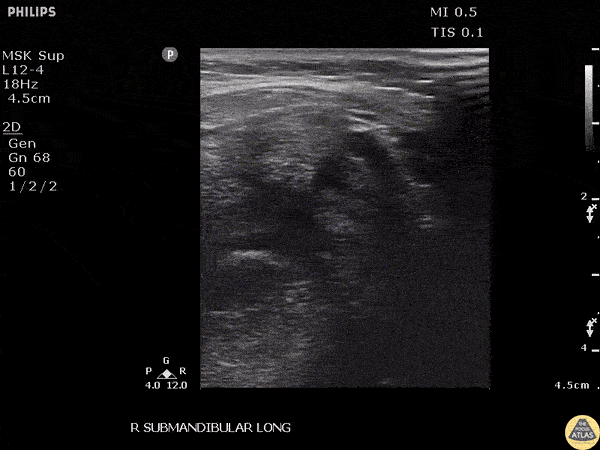

A male presented to the ED with submandibular pain and swelling. Ultrasound revealed a 0.942 cm stone within the submandibular gland. Image courtesy of Robert Jones DO, FACEP @RJonesSonoEM Director, Emergency Ultrasound; MetroHealth Medical Center; Professor, Case Western Reserve Medical School, Cleveland, OH View his original post here